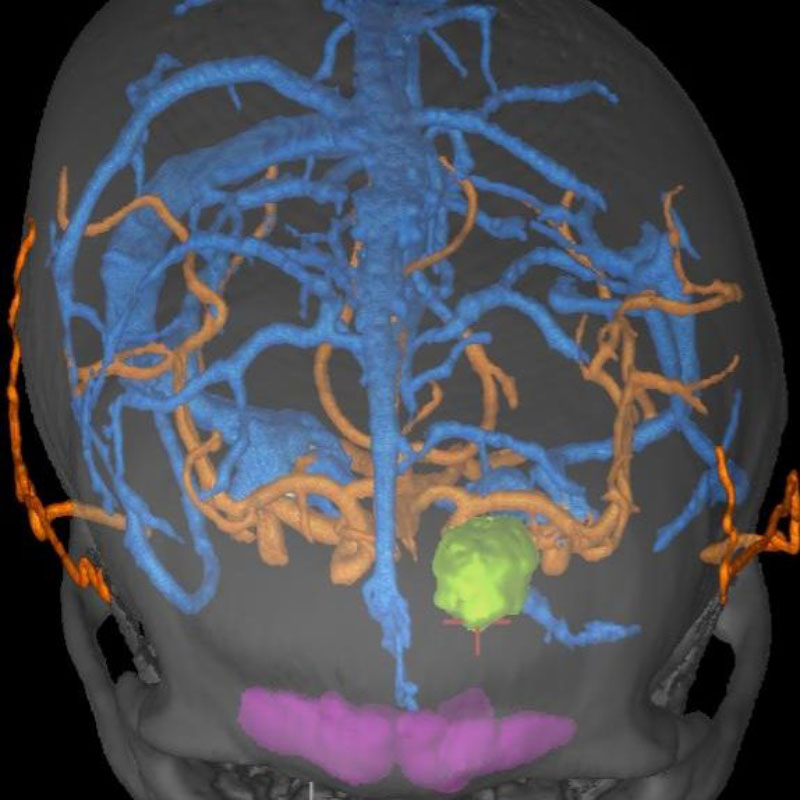

脳幹部

海綿状血管腫

出血の予防目的

熊本県の病院

No.No.62 手術前1

No.No.62 手術前2

No.No.62 手術後1

No.No.62 手術後2

CT/MRにより完全に摘出されたことが確認された